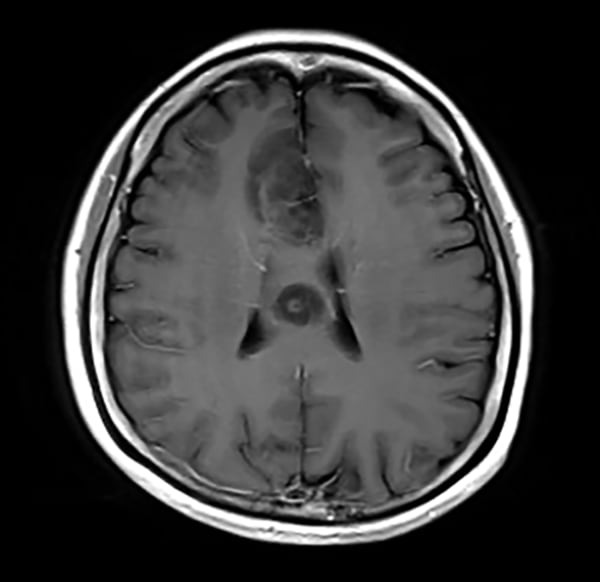

T1WI低信号、T2WI高信号、FLAIR高信号、DWIでやや高信号の腫瘤。Gdで腫瘤は造影されず、DSC-Perfusionでは辺縁~中心部に一部血流の高い部分あり。MRスペクトロスコピーではCho上昇とNAA低下がみられる。Low grade gliomaを疑う。後日、摘出手術が施行され、病理診断はoligodendroglioma NOS(Grade 2)であった。